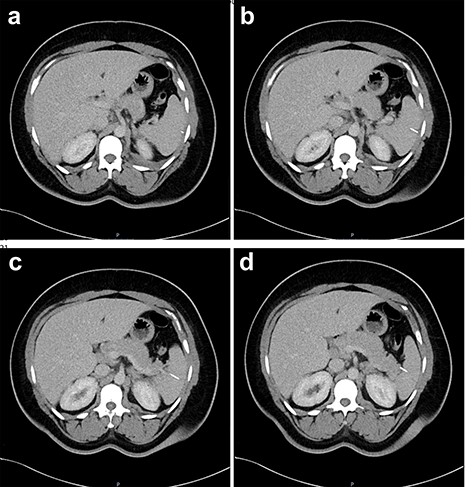

Two-mm axial sections from a CT scan demonstrating the linear hyperdensity traversing the spleen across multiple cross sections. (a) Section number 65 (b) section number 67 (c) section number 69 (d) section number 71 (e) section number 73 (f) section number 75.

Two-mm axial sections from a CT scan in January 2020, performed after the VATS procedure, to check resolution of the empyema that shows the foreign body impacted in the spleen without evidence of haematoma. (a) section number 18, (b) section number 19, (c) section number 20, (d) section number 21.